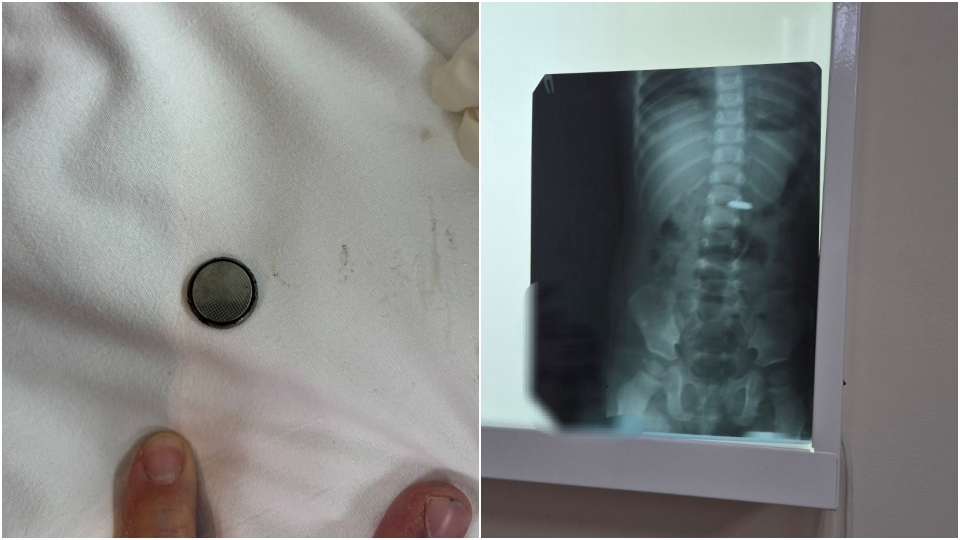

Ребенок проглотил или нет

Ребенок проглотил или нет 103 фотографий